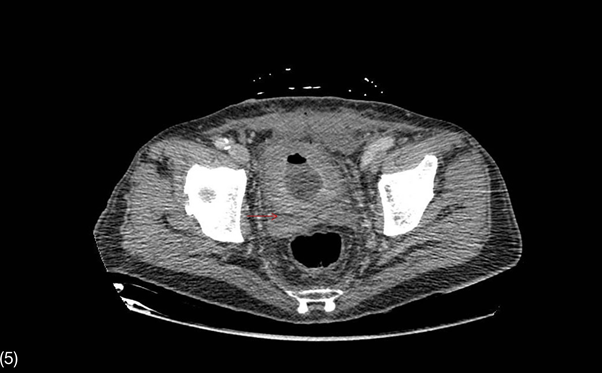

Figure 5 Contrast-enhanced CT scan of the abdomen in sagittal view.

Thickened bladder walls with emphysema around the prostate.